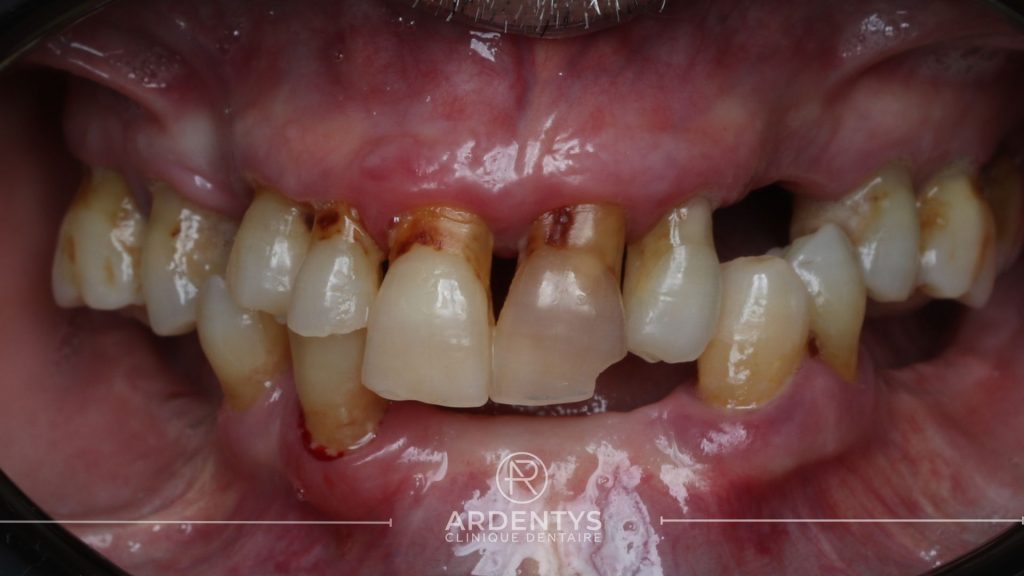

Réhabilitation complète bi maxillaire